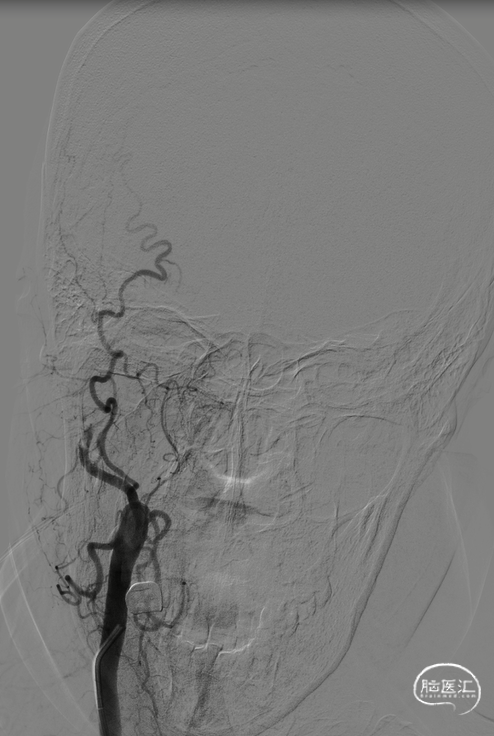

术前造影

右侧颈内动脉闭塞,同时颈外动脉有血栓,闭塞。

右侧颈内动脉起始部呈现“火焰征”,提示假性闭塞,远端眼动脉未见代偿。

前交通开放,左侧A1供应双侧A2。

后交通动脉开放,右侧大脑中动脉可见部分显影。